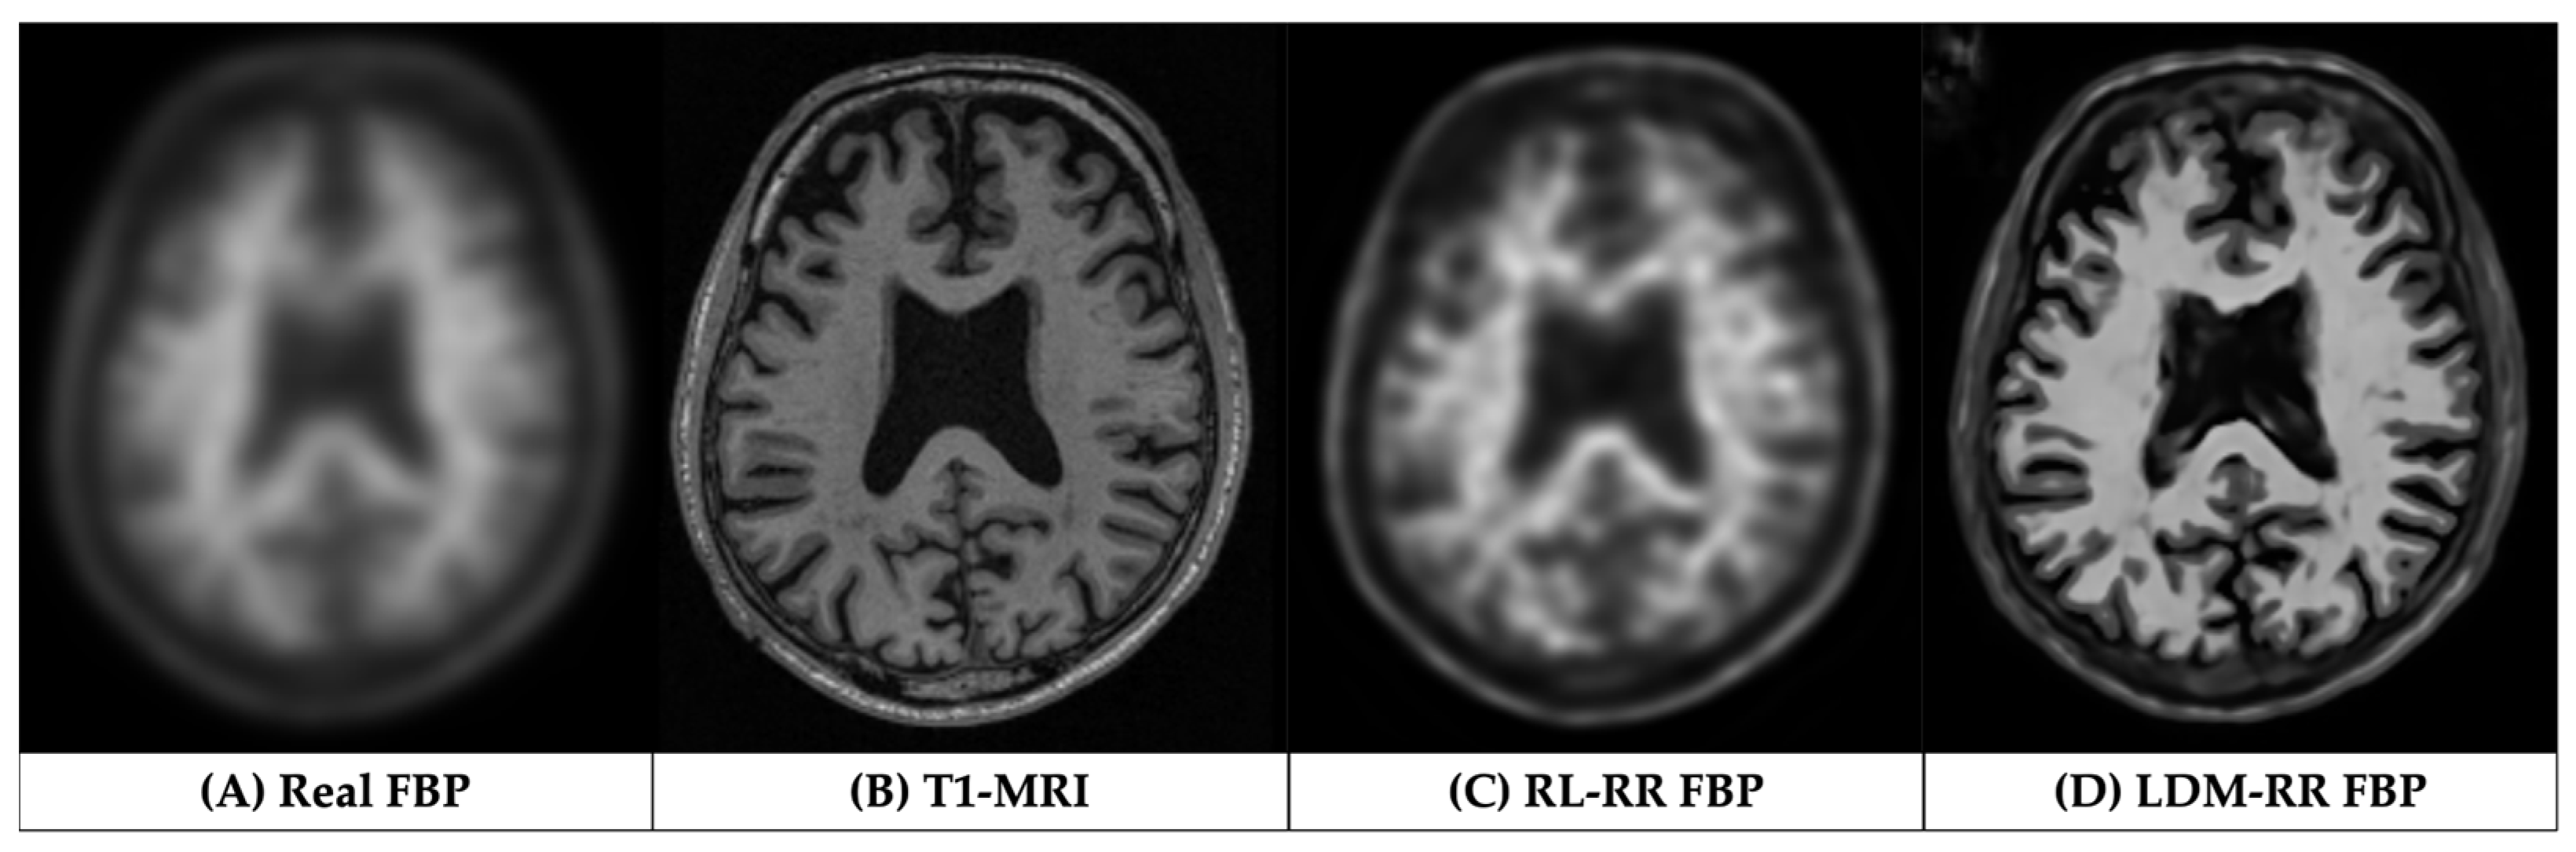

3.1. Qualitative Assessments